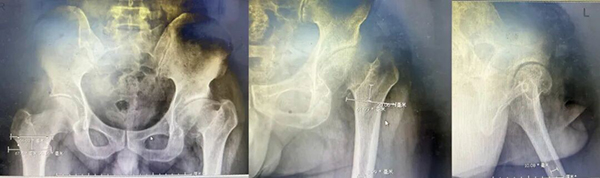

术前X线:

来到生态城医院骨科后,检查结果揭开了真相:左侧股骨头缺血性坏死(ARCO分期Ⅳ期)——股骨头已经塌陷变形,保守治疗已无能为力。